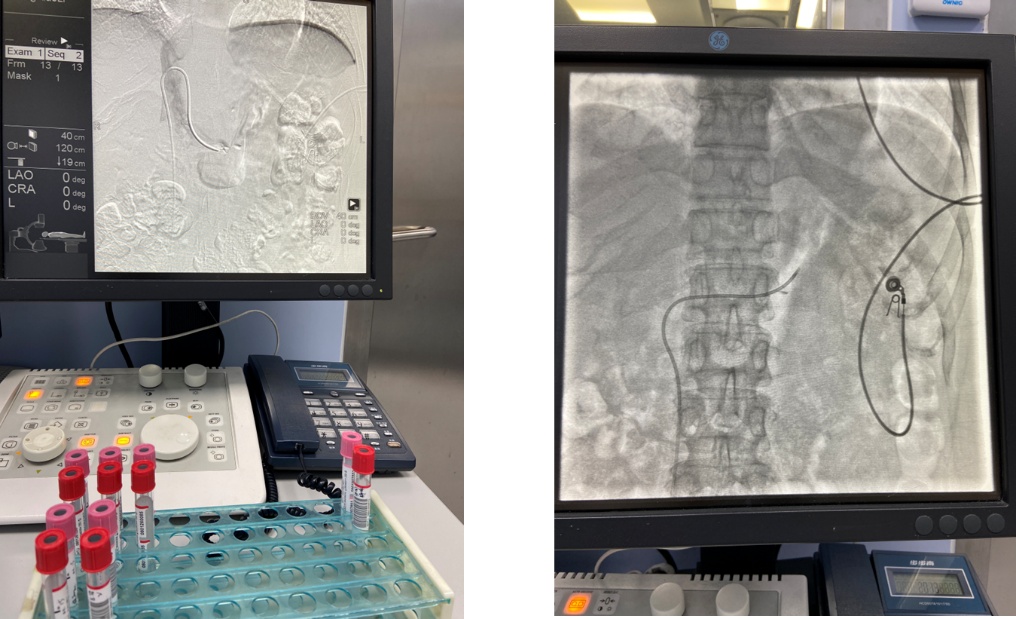

程飚主任通过病史询问、查体及相关影像学检查,认为李女士的症状的确是臀肌挛缩症,可行关节镜微创治疗。入院后,程飚主任团队完善术前检查及相关术前准备,为李女士进行了关节镜下双侧臀肌挛缩松解术,手术效果很好,双侧臀部紧张的挛缩带充分松解,手术切口非常小。术后结合康复治疗,目前李女士亦可并腿下蹲,活动时双侧髋部的弹响也消失了。李女士对此次就医非常满意,对程飚主任及其团队精湛的医术高度赞扬,向程飚主任表示衷心的感谢。

关节镜技术成为臀肌挛缩松解术的主流术式。关节镜下臀肌挛缩松解术疗效显著。通过关节镜技术,可在直视下,安全精准地松懈挛缩带。不仅疗效更加显著,手术切口不到1cm,美容化缝合,术后无需拆线,出血量少,手术时间大大缩短。患者术后疼痛轻,术后第二天即可下床活动并开始康复功能锻炼,切口美观,可最大程度上帮助大家早日恢复正常生活,给臀肌挛缩患者带来更全面的获益。